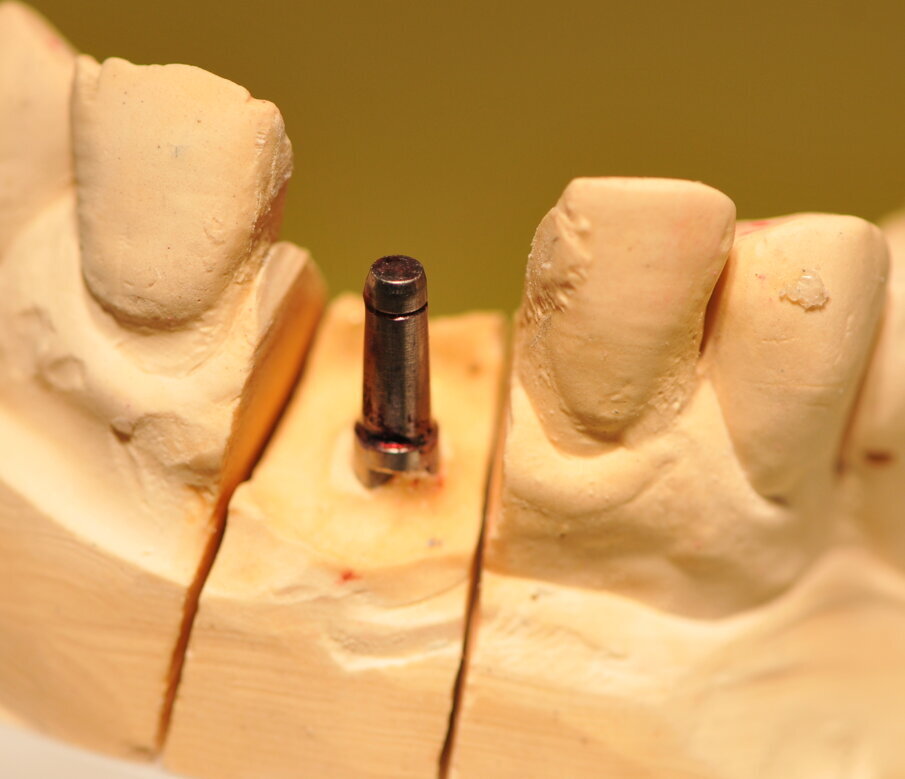

Fig. 7_Analogo del moncone sul modello in gesso.

Paziente di sesso maschile di 60 anni di età giunto alla nostra osservazione per una edentulia parziale dovuta all’assenza dell’elemento 1,1. La situazione clinica è resa esteticamente e funzionalmente complicata dalla assenza dell’elemento 2,2 che considerato lo spostamento dei denti contigui comporta un aumentato spazio per la sostituzione protesica dell’elemento 1.1. Si effettua dopo rx di controllo il posizionamento di un impianto osteintegrato GTB diametro 3,6 x 9 mm ,con posizionamento, come da protocollo, 1,5 mm sottocrestale ed inserzione immediata di moncone easy abutment slim 3,4 x 7 mm altezza gengivale 3,5 mm. angolato a 10 gradi (Easy Abutment Slim – GTB Plan1Health Amaro, UD, Italy). Con l’ausilio di una cappetta easy si costruisce e si cementa, con tecnica extraorale, una corona provvisoria in resina acrilica con forma a pontic su elemento 1.1 in modo da eseguire un carico immediato e fornire al paziente una estetica immediata (Figg. 1-3). Dopo 12 settimane ad avvenuta osteointegrazione si provvede all’impronta definitiva eseguita a livello abutment con elastomero di precisione Aquasyl Monophase (Dentsply) e con idonea cappetta easy (GTB Plan1Health Amaro, UD, Italy). La stessa cappetta easy viene utilizzata dal laboratorio odontotecnico come cappetta da sovrafusione garantendo standard di precisione stabiliti industrialmente (Figg. 4-8). La corona costruita in lega preziosa e porcellana viene cementata dopo una settimana, fatte le prove estetiche e occlusali necessarie sul paziente. I controlli a distanza di 4 anni, sia radiografici che clinici, confermano la stabilità dell’osso intorno all’impianto e la mancanza di perdita di tessuto gengivale attorno allo stesso (Figg. 9-11).